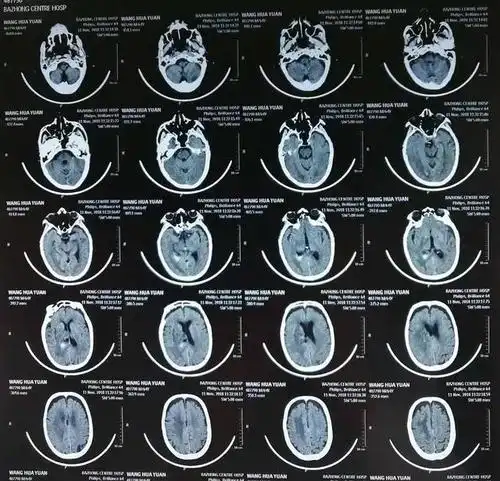

术后20天复查头颅ct基本正常

颅脑ct的正常解剖